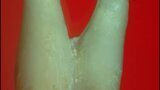

Buccal root of the bifurcated maxillary premolar—a danger zone during root canal therapy